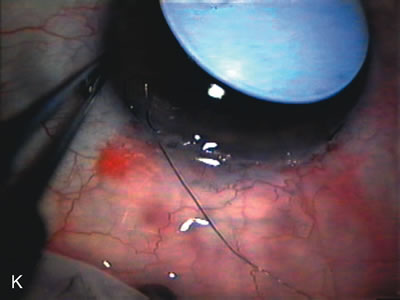

CATARACT EXTRACTION ALONE REDUCES IOP IN MOST EYES WITH ANGLE-CLOSURE GLAUCOMA

Uncomplicated cataract extraction substantially reduces IOP, along with the number of postoperative glaucoma medications in eyes with angle-closure glaucoma.146,147 When preoperative gonioscopy reveals PAS, along with adjacent areas of appositional closure, lens extraction alone in select cases may be a reasonable alternative to filtration surgery.148,149 Phacomorphic angle-closure disease due to enlargement of the lens with progressive angle crowding is eliminated following lens extraction. The width and depth of the anterior chamber angle in eyes with angle-closure glaucoma increases significantly after cataract extraction with IOL implantation and becomes similar to open-angle glaucoma and normal eyes.150,151 (Fig. 5). Combining phacoemulsification, IOL implantation, and limited goniosynechialysis is effective in the treatment of cataract and chronic angle-closure glaucoma.152 Phacoemulsification with implantation of a foldable IOL is more effective in reducing IOP and improving visual acuity than surgical peripheral iridectomy in eyes with acute angle-closure glaucoma.153

Fig. 5. Anterior chamber angle changes associated with lens extraction and PCIOL This 65-year-old Vietnamese woman has a long-standing history of chronic angle-closure glaucoma treated with laser peripheral iridectomy. The optic nerve demonstrated mild glaucomatous damage and IOP was moderately controlled on two antiglaucoma medications. The cataract was removed through temporal clear corneal phacoemulsification with foldable acrylic IOL. A. Symptomatic cataract in narrow-angle glaucoma eye with patent iridectomy. B. Intraoperative goniophotograph showing crowding of angle with increasing narrowness due to phacomorphic component. C. Intraoperative photograph showing temporal clear corneal approach with IOL in the capsular bag. D. Intraoperative goniophotograph demonstrating deepening of chamber angle following lens extraction. Proposed theories for IOP reduction following lens extraction with complete wound closure:

1. Anterior chamber deepening with improved access to trabecular meshwork

2. Increase in traction on the trabecular meshwork

3. Improved outflow facility mediated by an increase in prostaglandin release

4. Reduction in aqueous humor production

5. Atrophy of ciliary body processes

6. Goniosynechialysis due to intraoperative over deepening of AC with viscoelastic

7. Relief of undiagnosed pupil block